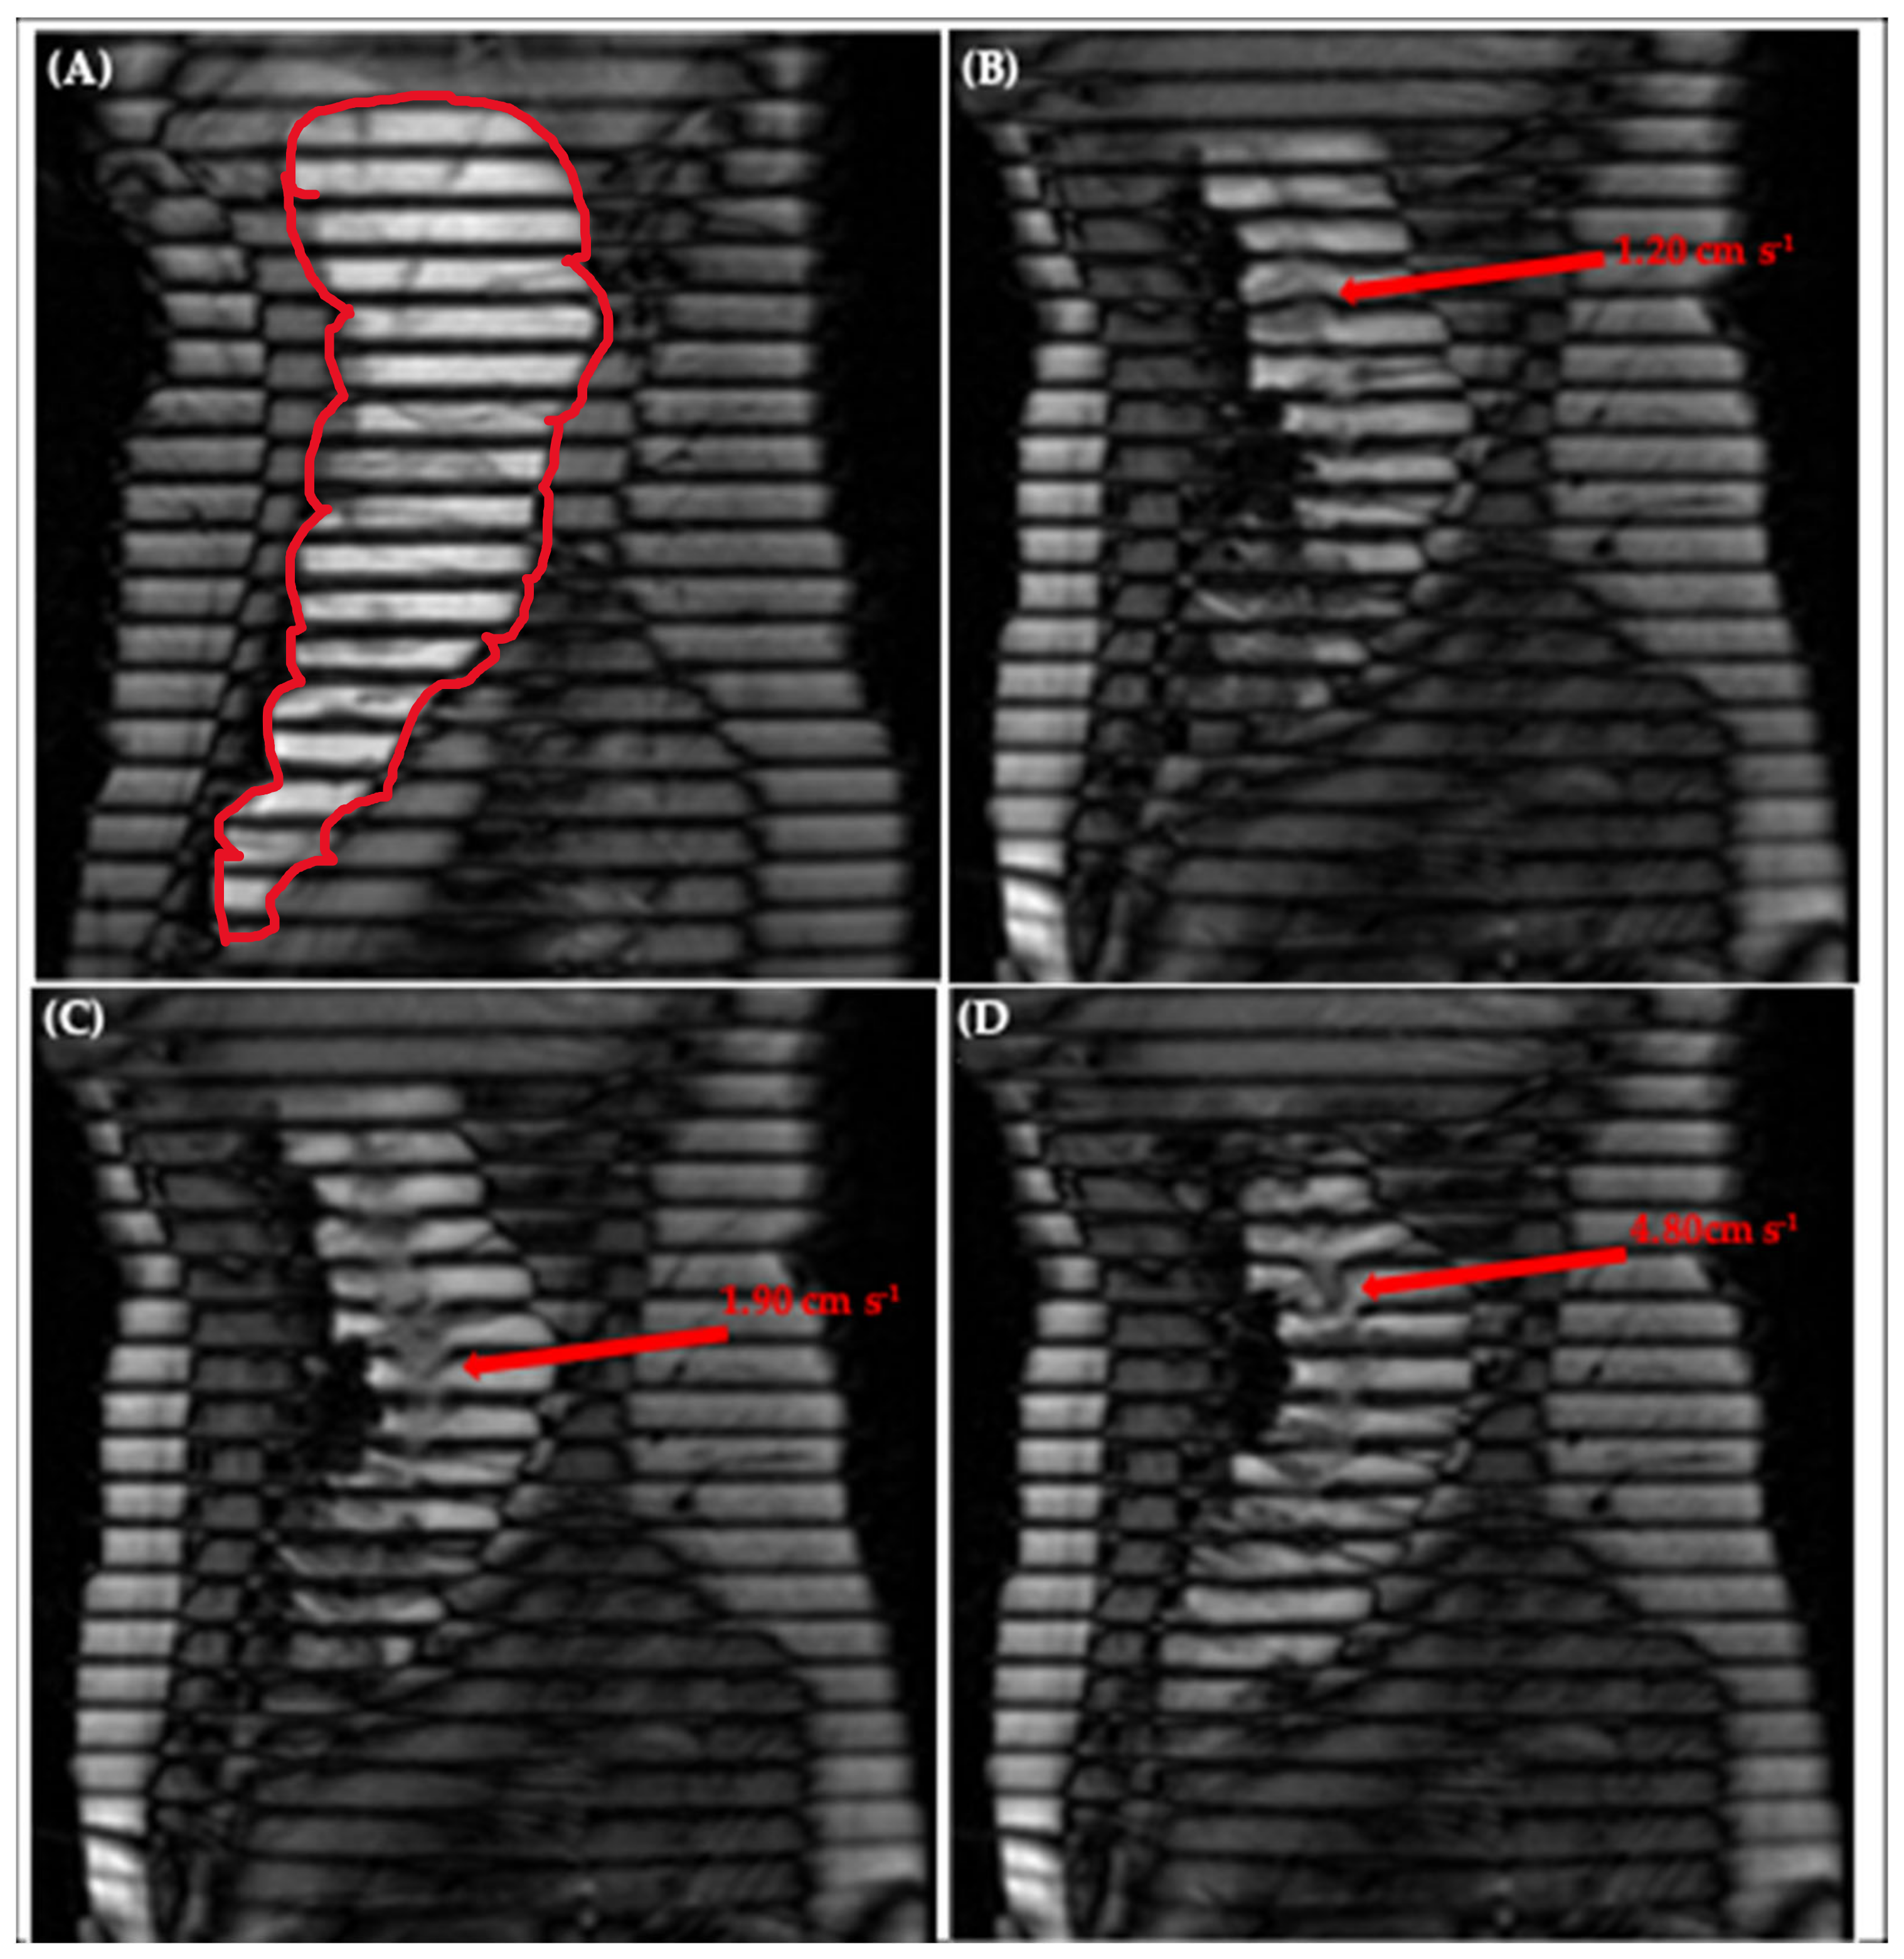

Figure 6A shows an image of the human ascending colon under baseline conditions with little to no motion, illustrated by the straight, parallel tags [20]. Figure 6B–D depicts a chronological selection of screenshots from Video S2, an in vivo tagged MRI sequence previously published by Pritchard et al. [20]. The opening sequence in video S2 begins with a contraction of the colonic walls close to the caecum, driving an antegrade wave of motion of the contents, with a residual velocity of 1.20 ± 0.20 cm·s−1, clearly shown further along the colonic axis in Figure 6B. Subsequently, the walls of the colon relax, dilating the lumen and driving the contents back towards the caecum in a wave of backflow first observable closer to the midpoint in the early frames of Video S2 and in Figure 6C and peaking with the following sharp jet of 4.80 ± 0.20 cm·s−1 shown in Figure 6D. The correlation between wall motion and flow events observed in this in vivo sequence is reproduced well in the DCM, as shown in Figure 2 and discussed in Section 3.1. This bolsters the DCM as a tool for enhanced biorelevant dissolution testing and demonstrates its suitability for the development of methods capable of achieving IVIVCs or performing IVIVE for colon-targeted formulations.

Figure 6.

Tagging applied to the ascending colon, outlined in red in (A), showing (A) little motion, (B) antegrade flow of 1.20 ± 0.20 cm·s−1 close to the hepatic flexure, (C) retrograde flow of 1.90 ± 0.20 cm·s−1 close to the midpoint of the AC and (D) retrograde ‘jet’ of 4.80 ± 0.20 cm·s−1 close to the hepatic flexure. Images taken from supplementary video S2 of Pritchard et al. [20].

Thus, measurement of velocity of the tagged colonic contents under stimulated conditions in vivo was possible, with many tags remaining intact, permitting local velocity measurement at different spatiotemporal locations along the colonic axis. This facilitated the evaluation of regional and temporal similarities and differences. For example, both antegrade (1.20 ± 0.20 cm·s−1) and retrograde (4.80 ± 0.20 cm·s−1) flows were measured close to the caecum, whilst close to the midpoint of the human AC, retrograde flows of 1.90 ± 0.20 cm·s−1 were recorded. Similar antegrade and retrograde activity has been reported in vivo by [30]. In conjunction with visualisation of how the walls moved in real time, this methodology therefore has the potential to further inform an understanding of colonic pathophysiology. A clear application would be to establish quantitative limits that identify regions suffering from dysmotility based on the magnitude of the velocity of the contents compared to values observed in the healthy AC. A key advantage of the tagged MRI technique is the coverage acquired—the ability to both visualise and measure flows across the entire AC in one scan.

Complex multidirectional flows were observed under stimulated in vivo conditions, manifesting as smearing of the tag lines, and simultaneous antegrade and retrograde flow of media at different points along the same tag, as shown in Supplementary Materials Video S2 and Figure 6C,D. These phenomena were not observed in the DCM, where tagged media typically flowed in a laminar antegrade or retrograde fashion. The DCM motility was programmed to replicate CPPWs in the healthy human colon, as opposed to the extreme stimulated conditions observed in the in vivo study of [20]. This involved a cyclic repetition of one antegrade CPPW in which all haustra in a segment contracted or relaxed in a specific, predefined order and with a fixed degree and rate of occlusion. In vivo, motility is governed by the enteric nervous system which results in a more complex motion than the controlled wall motility of the DCM. However, the in vivo motility observed by Pritchard et al. [20] included both antegrade and retrograde waves, with haustra contracting and relaxing asynchronously and with different degrees of occlusion, which due to the momentum of the contents, caused more complex multidirectional flows. Similar activity has been observed in vivo by Wilkinson-Smith et al. [16], where contractions in the AC wall were not continuous, but sporadic. Multidirectional motility patterns could be replicated in future work with the DCM to more precisely mimic specific in vivo patterns for direct comparison. Furthermore, there are many other factors associated with administration of the stimulus that may affect the motility in vivo. For example, the rate of delivery of macrogol to the AC, the mixing of the macrogol with the contents of the colon upon arrival and the absorption rate of any fluid from the macrogol [16]. These factors, in addition to characteristics of the patient such as age [40], influence the volume of the contents of the AC, which is likely to trigger distension of the walls in vivo, hence driving the erratic motility. In vitro, the DCM was only partially filled (150–200 mL, 52–69%), compared to the AC which was full of contents after the macrogol stimulus.